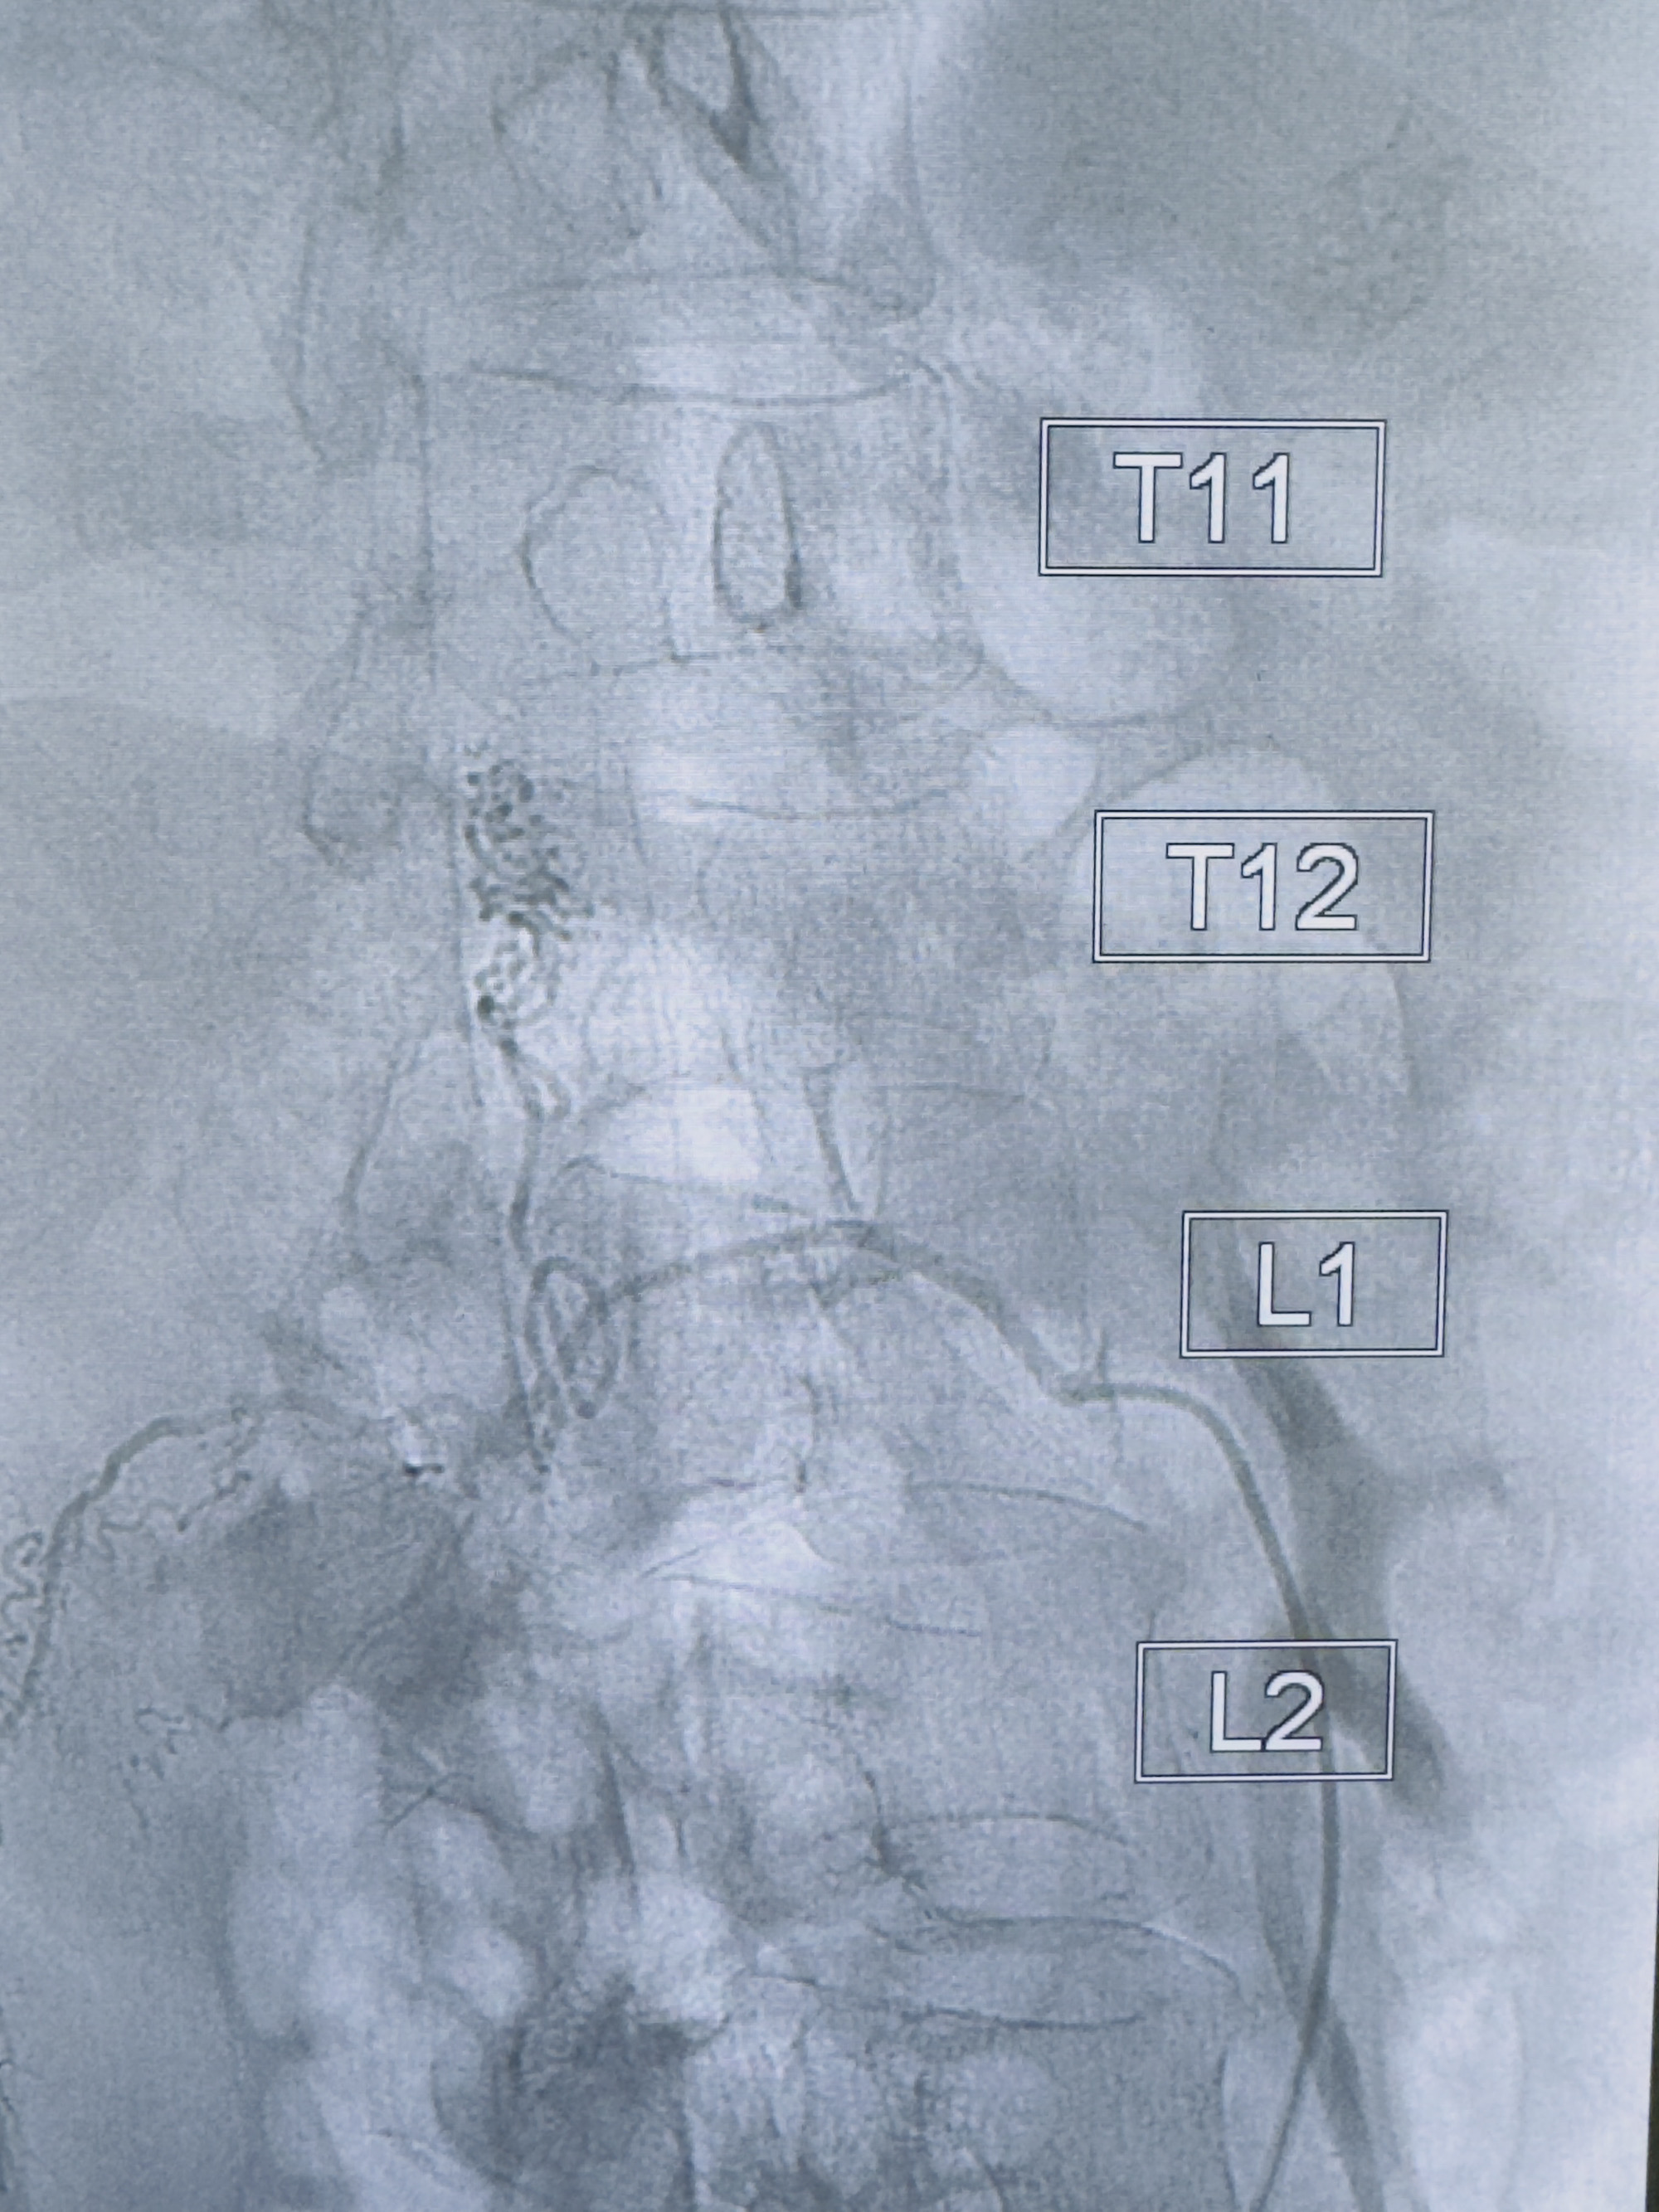

2023-10-13DSA:右侧L1水平硬脊膜动静脉瘘,供血动脉为右侧L1,附近动脉未见明确吻合供血,供血动脉处可见脊髓前动脉发出